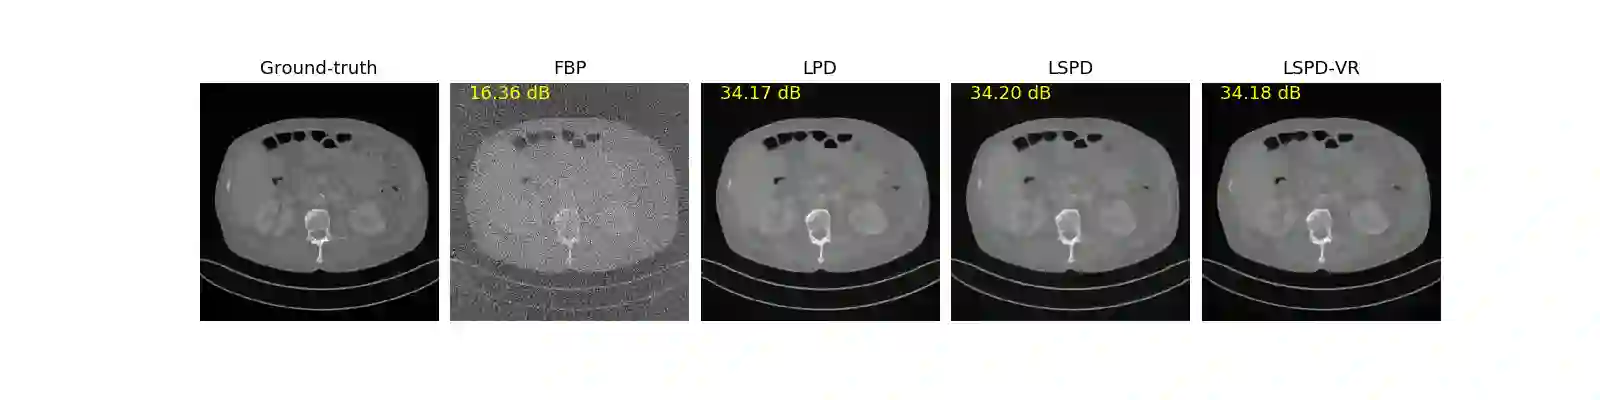

We propose a new type of efficient deep-unrolling networks for solving imaging inverse problems. Conventional deep-unrolling methods require full forward operator and its adjoint across each layer, and hence can be significantly more expensive computationally as compared with other end-to-end methods that are based on post-processing of model-based reconstructions, especially for 3D image reconstruction tasks. We develop a stochastic (ordered-subsets) variant of the classical learned primal-dual (LPD), which is a state-of-the-art unrolling network for tomographic image reconstruction. The proposed learned stochastic primal-dual (LSPD) network only uses subsets of the forward and adjoint operators and offers considerable computational efficiency. We provide theoretical analysis of a special case of our LSPD framework, suggesting that it has the potential to achieve image reconstruction quality competitive with the full-batch LPD while requiring only a fraction of the computation. The numerical results for two different X-ray computed tomography (CT) imaging tasks (namely, low-dose and sparse-view CT) corroborate this theoretical finding, demonstrating the promise of LSPD networks for large-scale imaging problems.